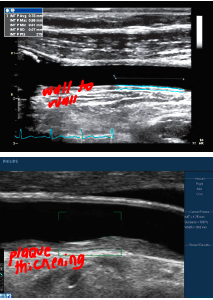

what is are these images demonstrating?

atherosclerotic plaque early stage (Traditionally sonographically we don’t see any changes until step 3, fibrous plaque. Studies have shown intima- medial thickness measurements can “predict” further plaque development. With changes in life style and medication to slow process)

all Heterogeneous - mixed echoic pattern. Homogeneous is- uniform plaque texture

what type of plaqe is shown here?

smooth plaque

what type of plaque is this

irregular, complex. older, has been there longer b/c hyperechoic